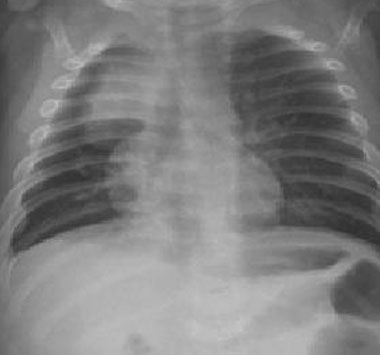

Figure 2 – Initial chest radiographs showed right upper lobe consolidation.

Laboratory tests and radiographic evaluation. Initial laboratory results indicated a slightly low ionized calcium level and an elevated alkaline phosphatase level. Chest radiographs showed right upper lobe consolidation (Figure 2). Pulmonology, ophthalmology, genetics, endocrinology, and gastroenterology specialists were consulted.